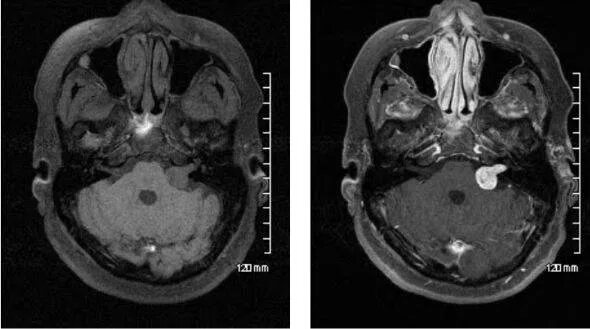

Мрт головного мозга мосто мозжечкового угла